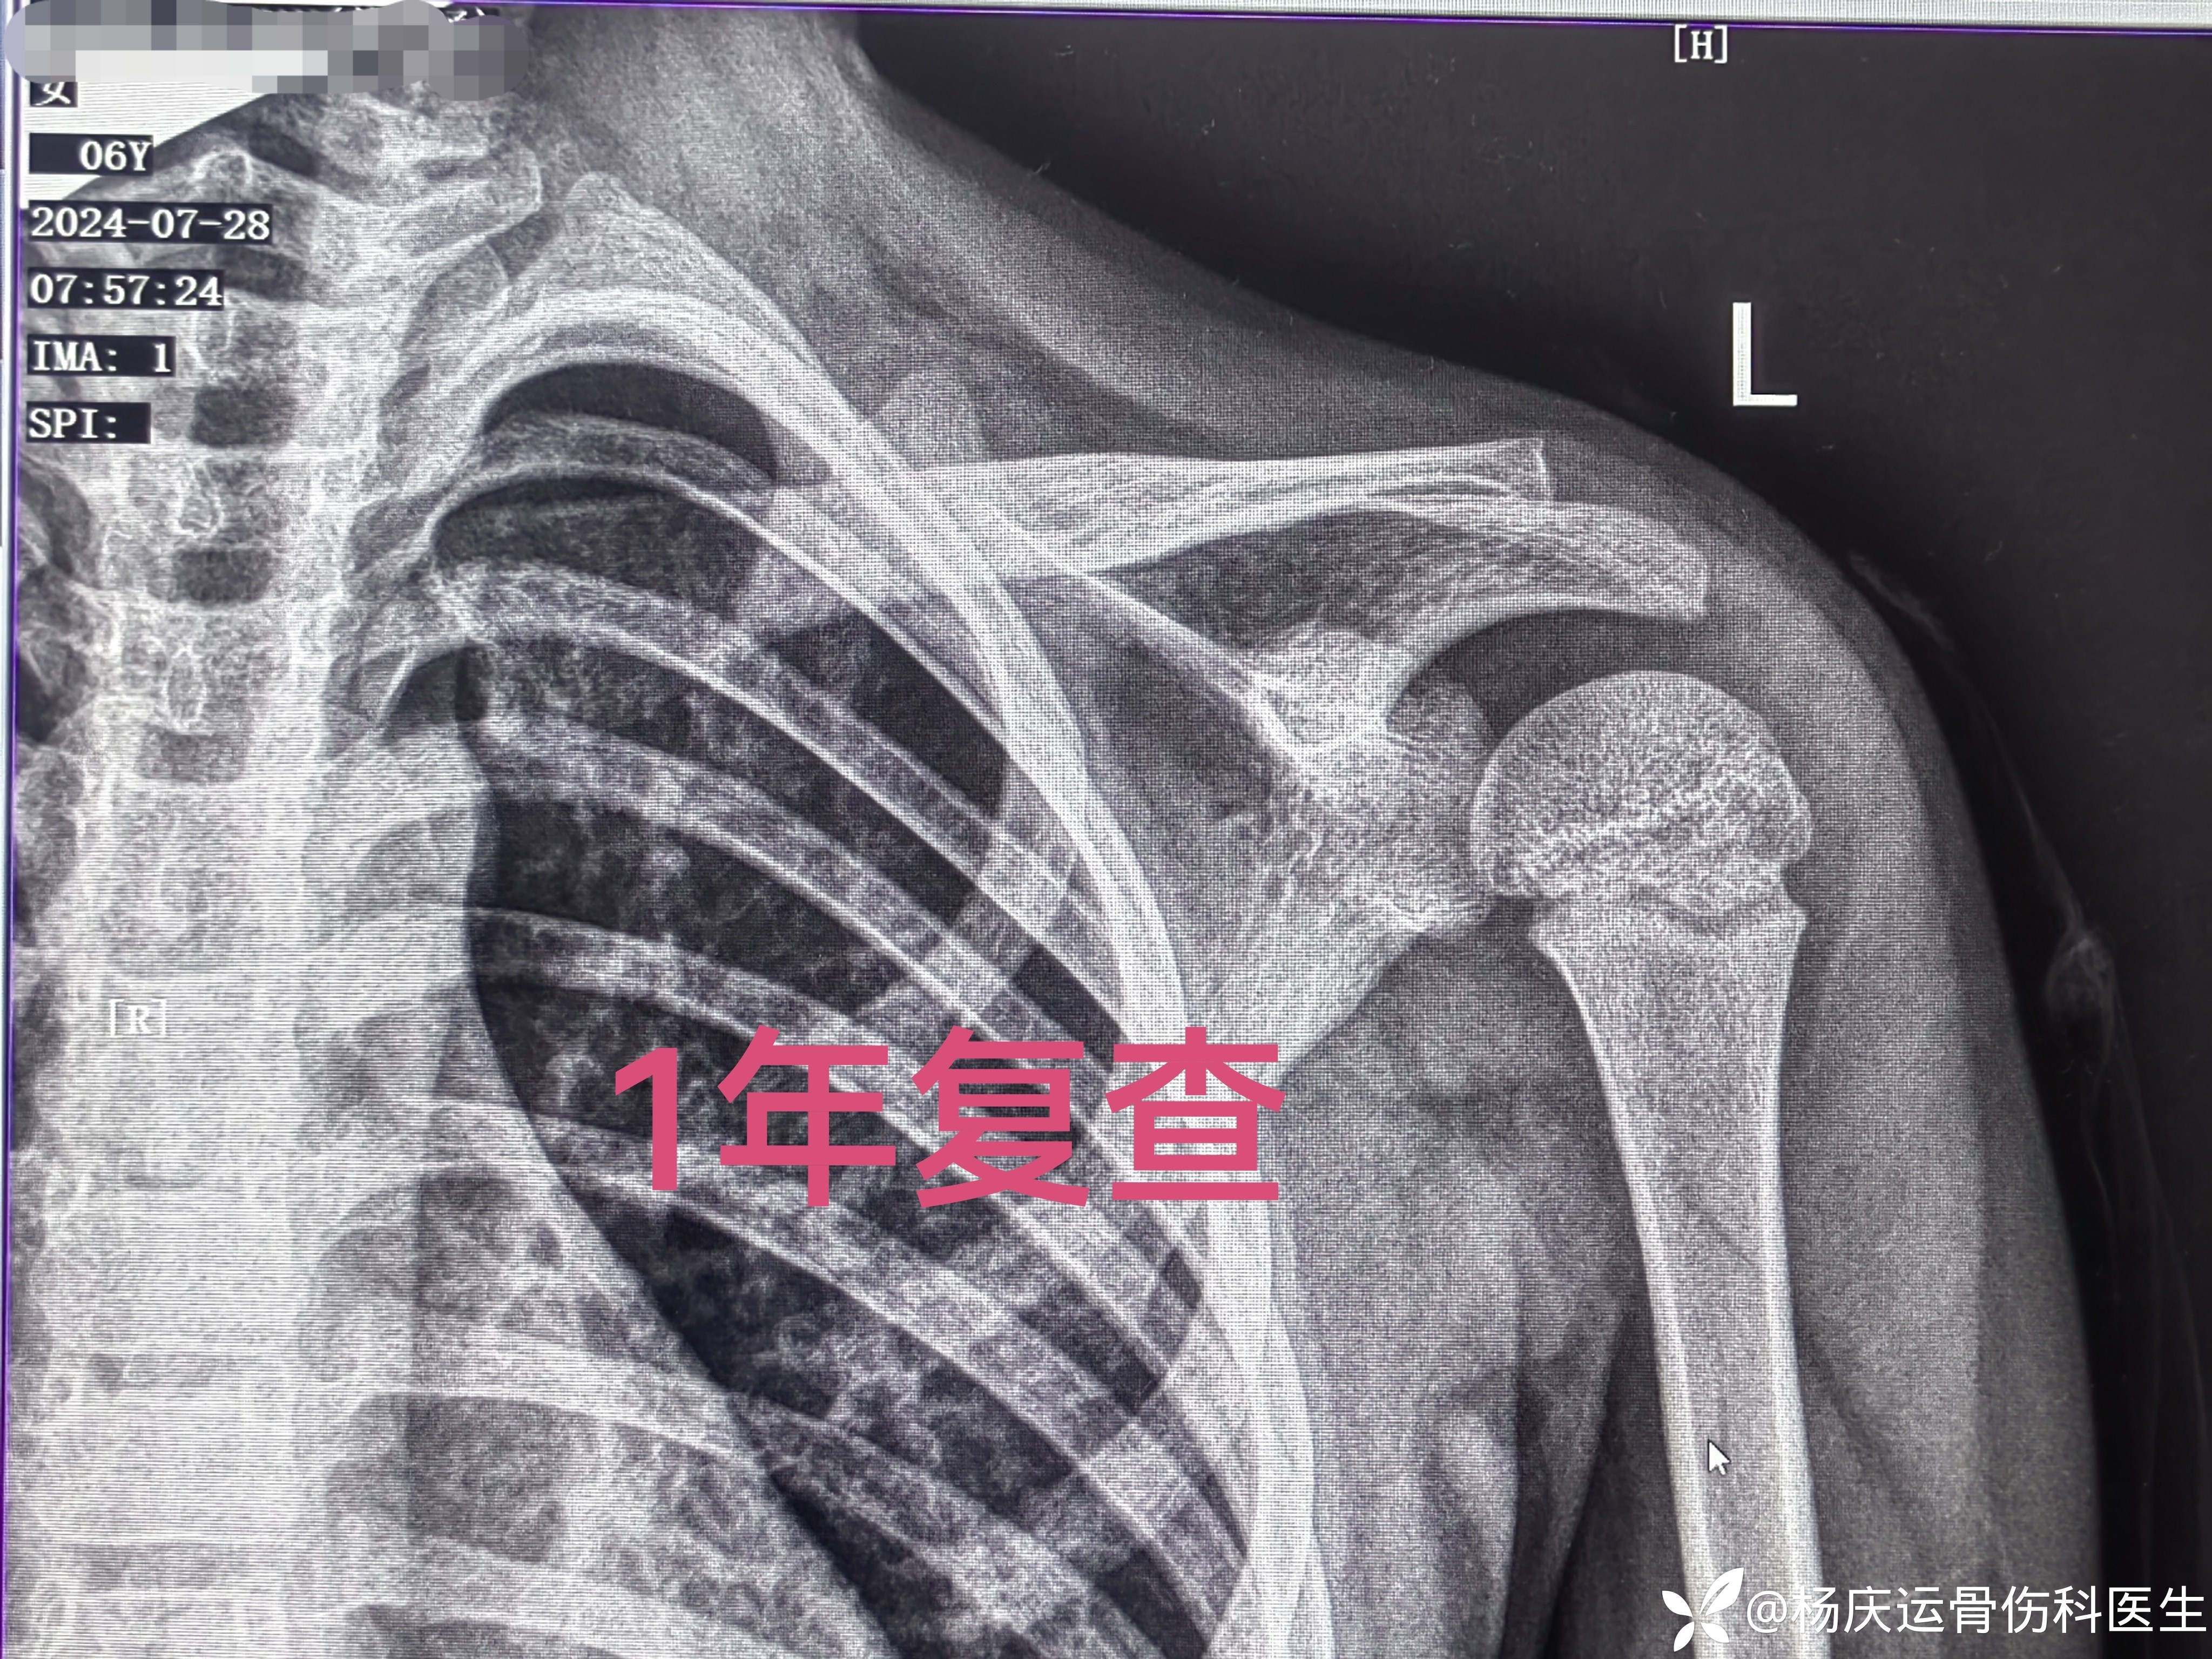

1年复查,完全重塑

功能恢复正常